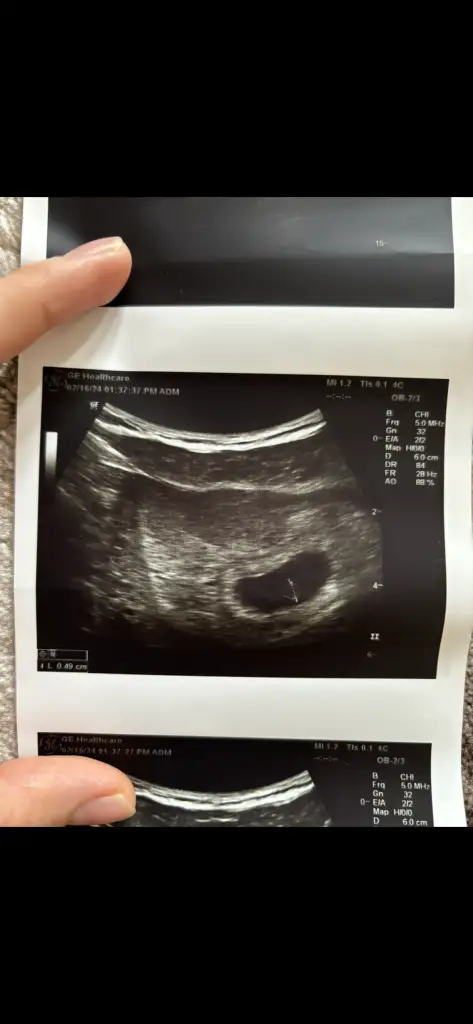

Kızlar iyi geceler hepinize. Bugün ilk kontrolüme gittim kalp atışını duyduk adet tarihim ile uyumlu çıktı. 6+2 dedi progestan verdi ağrım çok var diyince.